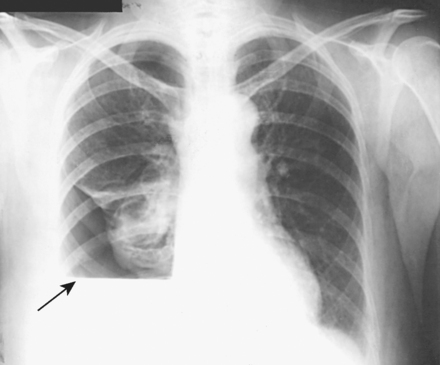

Structures shown: A lateral projection in the decubitus position shows a change in the position of fluid and reveals pulmonary areas that are obscured by the fluid in standard projections (Figs. 10-66 and 10-67).

Fig. 10-66 Right lateral projection, dorsal decubitus position. Arrows indicate air-fluid level. Note correct marker placement, with upper side of the patient indicated.

Fig. 10-67 Upright PA chest in same patient as in Fig. 10-66. Note right lung fluid level (arrow).